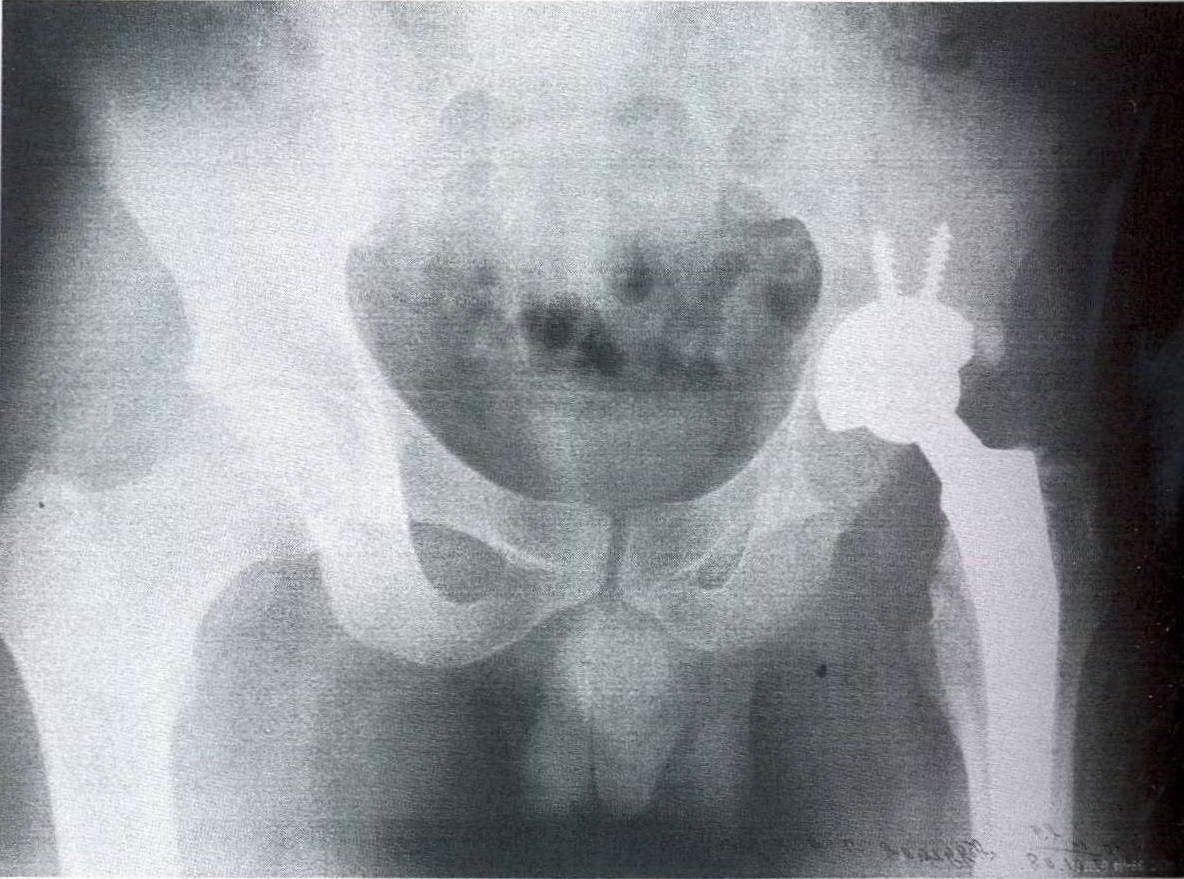

Фотографии и схемы: Коксит правого тазобедренного сустава